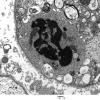

PERIPHERAL NEUROPATHY

4 AXONAL DEGENERATION

4 Macrophages